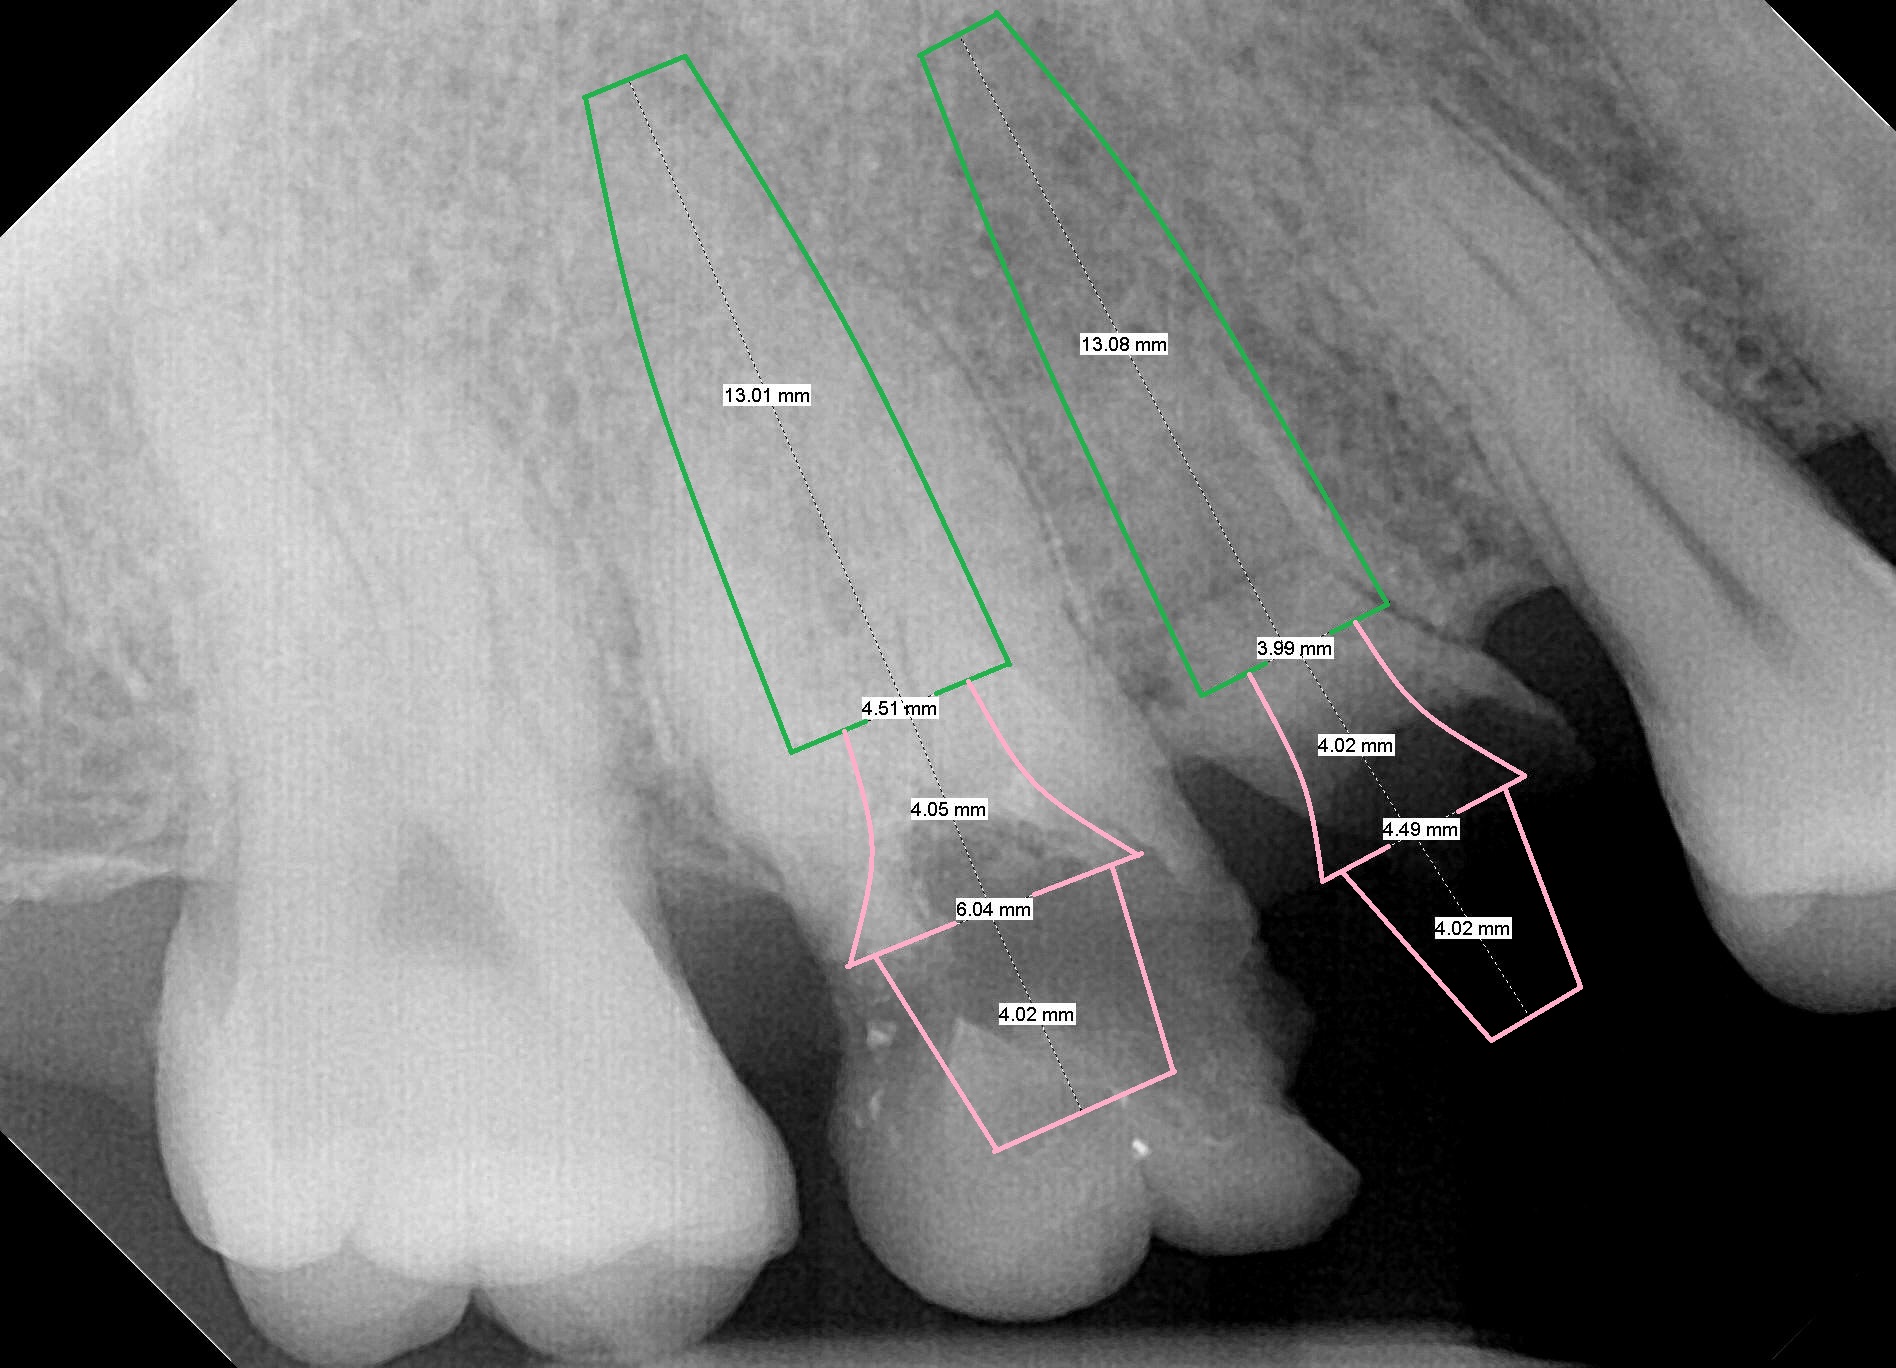

A 49-year-old woman (DC) requests treatment for residual roots at #3 and 4 after treatment of #9 (Fig.1). It appears that there will be no buccal or palatal wall defects. After extraction (no Antibiotic socket disinfection), osteotomy will be initiated with 1.6 mm pilot drill in the septum of #3, followed by Marking Bur (if the septum is pointed) and Magic Drill 3.3 mm for the full length (Fig.2), 3.8 mm for full length-2 mm. A 4.5 mm dummy implant is to be placed at #3 (underprep). If primary stability is low, place an implant of the next size. At #4 site, place a 4 mm dummy implant as palatal as possible (no prep). Measure the depth of the socket and the implant will be 1-2 mm shorter.